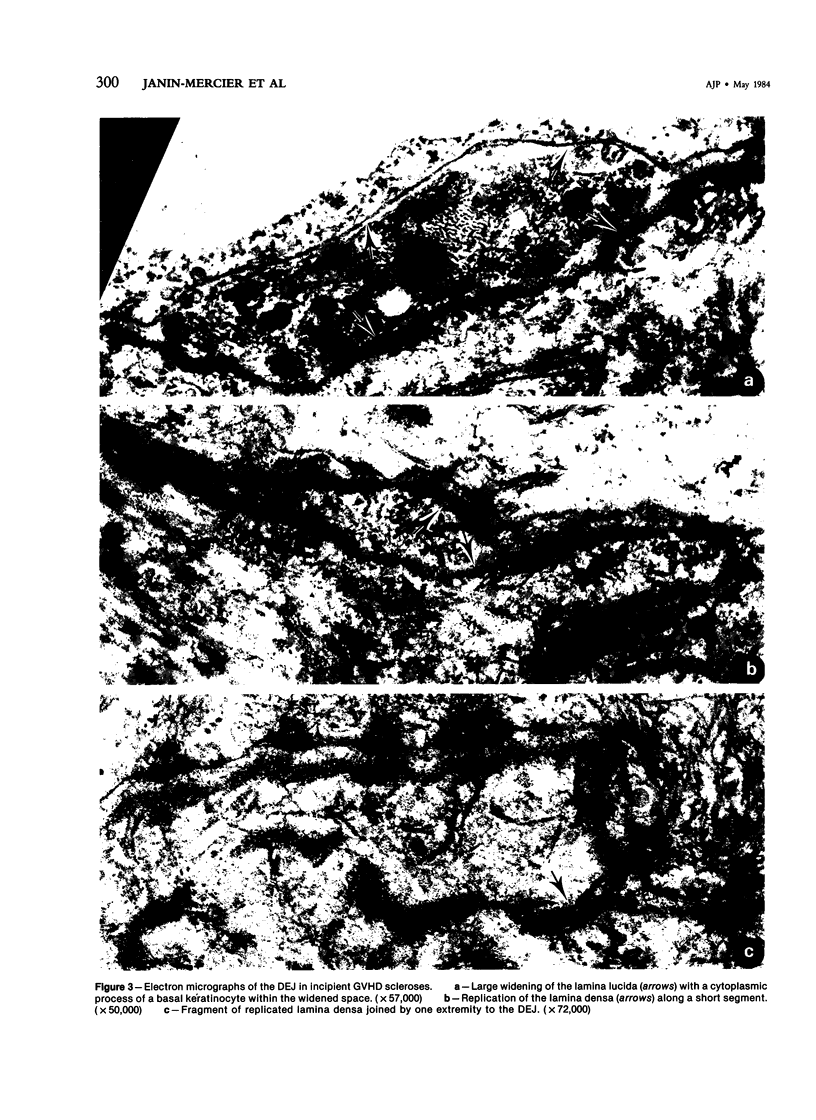

Thirteen skin biopsies were performed on 8 patients at different stages of skin sclerosis in chronic graft-versus-host disease (GVHD). On the same skin biopsies an immunostaining with antibodies directed against Types I and III procollagen, Types I, III, IV, V collagen, and laminin, and an ultrastructural study were performed. Alterations were observed at the dermal-epidermal junction and in the superficial dermis with a large deposit on Type III procollagen in the incipient scleroses and of Type I procollagen in the oldest ones. In this sclerotic superficial dermis, collagen fibers of irregular diameter were associated with mast cells and active fibroblasts, macrophages, and lymphocytes in close contact. The skin sclerosis in chronic GVHD might be considered a form of cutaneous fibrosis with features of excessive tissue repair related to an immunologic reaction between lymphocytes of the graft and tissue host cells.